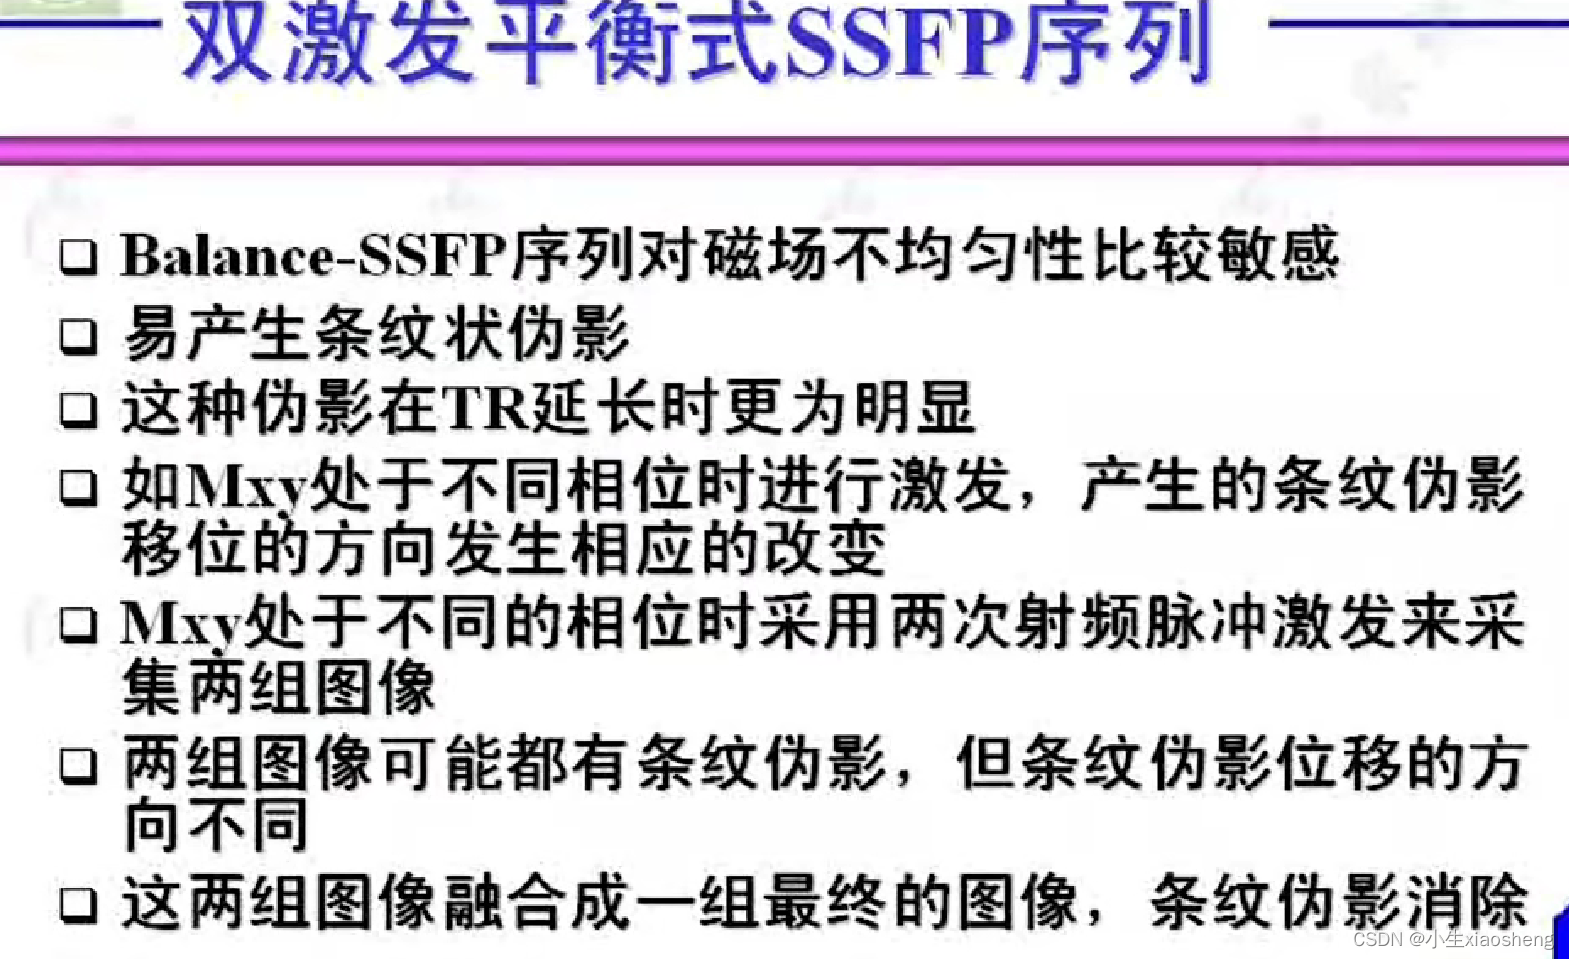

4.双激发平衡SSFP序列

双激发平衡SSFP序列在平衡SSFP的基础上进一步改进,通过两次激发来增强信号并改善图像质量。具体来说,它使用两个连续但相位相反的射频脉冲来激发质子。由于两次激发的相位相反,它们产生的信号在相位上相互抵消,从而减少了由于T1和T2差异导致的信号衰减或增长。这种技术可以提高图像的对比度和信噪比,特别是在需要高信噪比和快速成像的应用中。